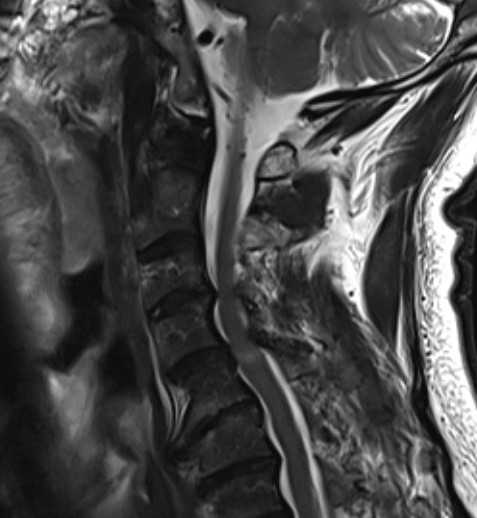

MRI

Stenosis

Cord injury

- high signal intensity on T2

- localise level of injury